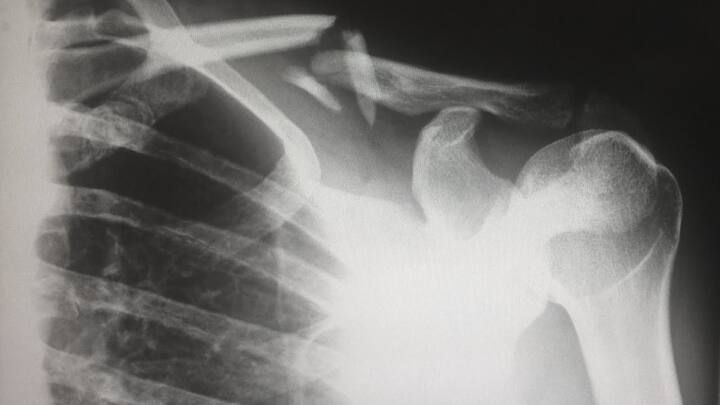

ਫੇਫੜੇ ਹਵਾ ਖਿੱਚ ਕੇ ਸਰੀਰ ਦੇ ਇੱਕ ਮਹੱਤਵਪੂਰਨ ਹਿੱਸੇ ਦਿਲ ਨੂੰ ਆਕਸੀਜਨ ਪਹੁੰਚਾਉਂਦੇ ਹਨ। ਦਿਲ ਇਸ ਆਕਸੀਜਨ ਨੂੰ ਦੂਜੇ ਅੰਗਾਂ ਨੂੰ ਸਪਲਾਈ ਕਰਦਾ ਹੈ। ਜੇਕਰ ਦਿਲ ਕੰਮ ਨਹੀਂ ਕਰਦਾ ਤਾਂ ਇਸ ਦਾ ਅਸਰ ਫੇਫੜਿਆਂ 'ਤੇ ਪੈਂਦਾ ਹੈ।

ਫੇਫੜੇ ਹਵਾ ਖਿੱਚ ਕੇ ਸਰੀਰ ਦੇ ਇੱਕ ਮਹੱਤਵਪੂਰਨ ਹਿੱਸੇ ਦਿਲ ਨੂੰ ਆਕਸੀਜਨ ਪਹੁੰਚਾਉਂਦੇ ਹਨ। ਦਿਲ ਇਸ ਆਕਸੀਜਨ ਨੂੰ ਦੂਜੇ ਅੰਗਾਂ ਨੂੰ ਸਪਲਾਈ ਕਰਦਾ ਹੈ।

ਜੇਕਰ ਦਿਲ ਕੰਮ ਨਹੀਂ ਕਰਦਾ ਤਾਂ ਇਸ ਦਾ ਅਸਰ ਫੇਫੜਿਆਂ 'ਤੇ ਪੈਂਦਾ ਹੈ। ਜੇਕਰ ਫੇਫੜੇ ਕੰਮ ਕਰਨਾ ਬੰਦ ਕਰ ਦਿੰਦੇ ਹਨ ਤਾਂ ਸਰੀਰ ਨੂੰ ਆਕਸੀਜਨ ਨਹੀਂ ਮਿਲੇਗੀ ਅਤੇ ਇਸ ਨਾਲ ਹਾਰਟ ਅਟੈਕ ਦਾ ਖਤਰਾ ਵਧ ਜਾਂਦਾ ਹੈ।